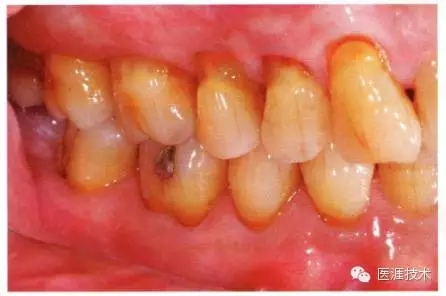

65歲男性。糖尿病與高血壓病史,目前治療中,40歲左右戒煙。有唾液減少傾向,但目前尚未見對牙齒及牙周組織的影響。初診時(shí)齲齒治療后,來院就診保養(yǎng)10年,雖因刷牙過度有牙齦萎縮,但牙齒及牙周組織仍保健康。如可妥善維持菌斑控制,則可維持牙周組織健康,不會減少牙周組織。